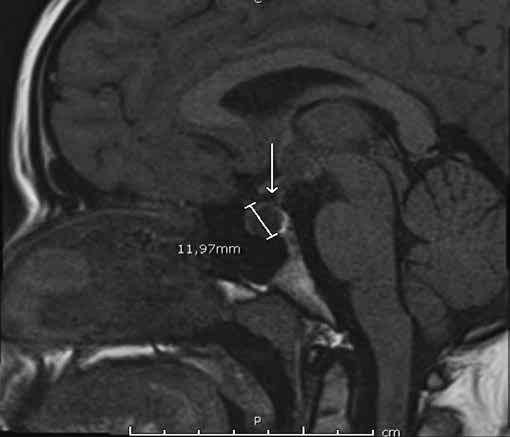

Figura 1a. RM de si a lla turca contrastada con gadolinio. Corte sagital en T1. Cortes 2.5 mm. Se señala región selar.

Se informa a continuación los estudios de imagen. Ecografía ginecológica (estudio previo indicado por ginecología): útero de forma y tamaño normal que mide 52 x 21 x 29 mm, endometrio de 5 mm, ovario derecho 25 x 18 mm, ovario izquierdo 28 x 17 mm. RM de silla turca: glándula hipofisaria aumentada de tamaño que mide 1,0 cm de altura, 1,9 cm de ancho, 1,2 cm anteroposterior, imagen de comportamiento quístico en las diferentes secuencias con realce homogéneo del parénquima glandular que rodea la lesión quística y se mantiene hipointensa en T1 (Figura 1a), tallo hipofisario en la línea media, quiasma óptico y estructuras vasculares sin compresión. En T2 se aprecia parénquima glandular hiperintenso (Figura 1b). Campo visual sin alteraciones.